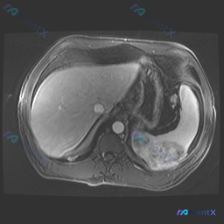

整理了一份肝脾同时出现多发占位的影像及鉴别思路,分享给大家。 --- 先看影像核心发现 这是一张增强腹部CT横断面(软组织窗): 1. 肝脏:肝左右叶弥漫分布多发、大小不一类圆形低密度灶,边缘相对清晰,部分病灶可见边缘强化/“靶征”; 2. 脾脏:脾脏实质内也有类似的低密度占位病变; 3. 其他:腹...

最近看到一份很有警示意义的腹部增强CT资料,整理一下思路和大家分享。 先看影像核心表现 这份是上腹部增强CT横断面软组织窗,主要异常集中在肝脏和脾脏: 1. 脾脏:体积稍大,脾实质内可见多发类圆形低密度结节灶,边界清晰,部分病灶边缘可见强化,呈「靶征」或「环形强化」改变。 2. 肝脏:肝实质内也可见...